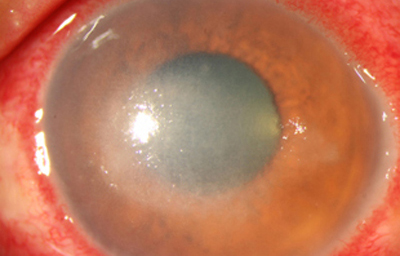

Superficie corneal irregular y grisácea, (Fig. 1, 2) con opácidades granulares en parche y formación de líneas epiteliales elevadas de aspecto granular (Fig. 3), que pueden arborizar dando imágenes de pseudodendritas. Opacidades superficiales satélites. (Figura 4) Inyección ciliar. Ulceración epitelial variante. (Figura 5).

Fig. 2 Síntomas de 25 días evolución